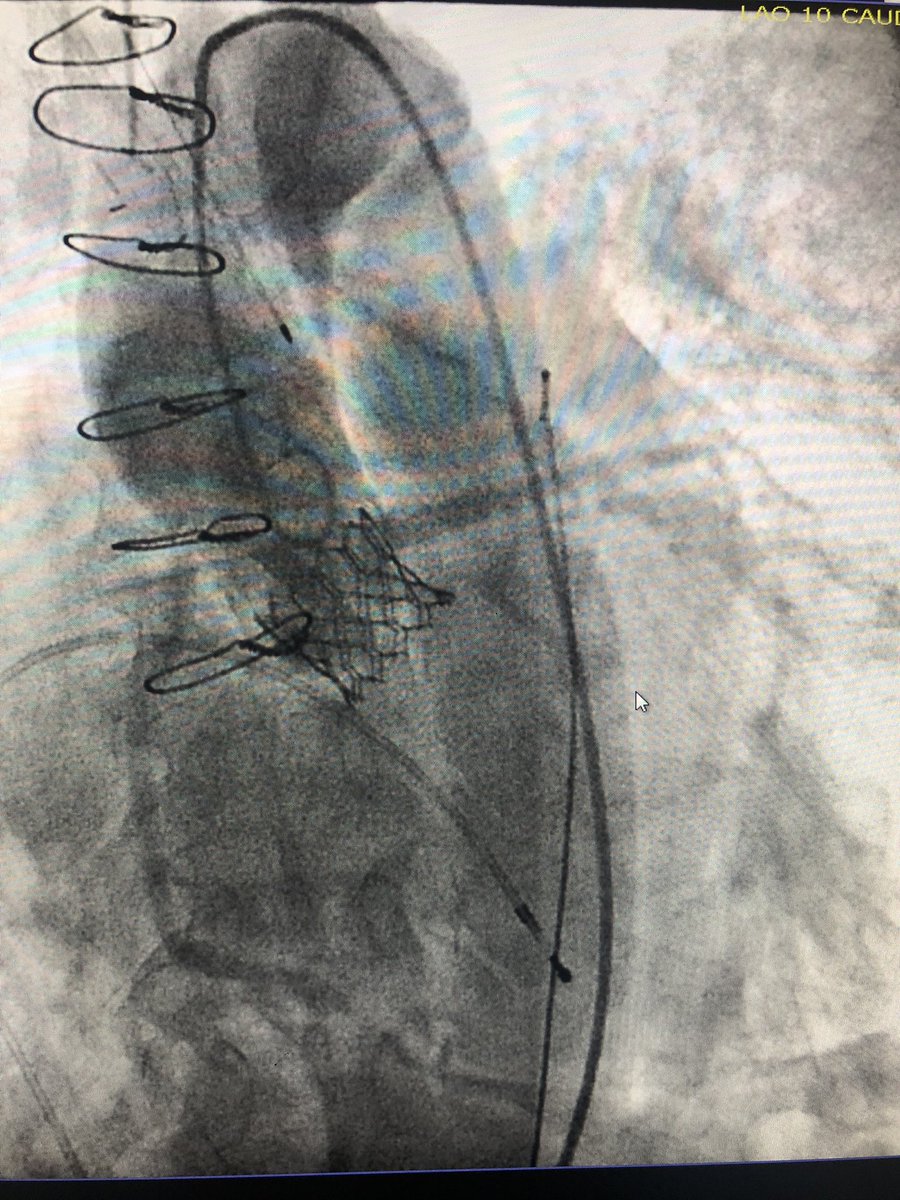

#TAVR #doubleprotection 56 yo f w/ SAVR 23 mm Freestyle. No CAD, ESRD. Severe prosthetic AS for ViV TAVR. Low RCA height at 6.8 mm and LCA at 8.1 mm. 23mm S3 deployed after protection of both coronaries. Post angio compromise of both cors. LM/RCA stents deployed w/ good result.

KaliyadanMD's tweet image. #TAVR #doubleprotection 56 yo f w/ SAVR 23 mm Freestyle. No CAD, ESRD. Severe prosthetic AS for ViV TAVR. Low RCA height at 6.8 mm and LCA at 8.1 mm. 23mm S3 deployed after protection of both coronaries. Post angio compromise of both cors. LM/RCA stents deployed w/ good result.